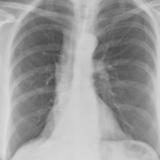

RLL Collapse 2 PA only

Date: 02/28/2004

Views: 3136